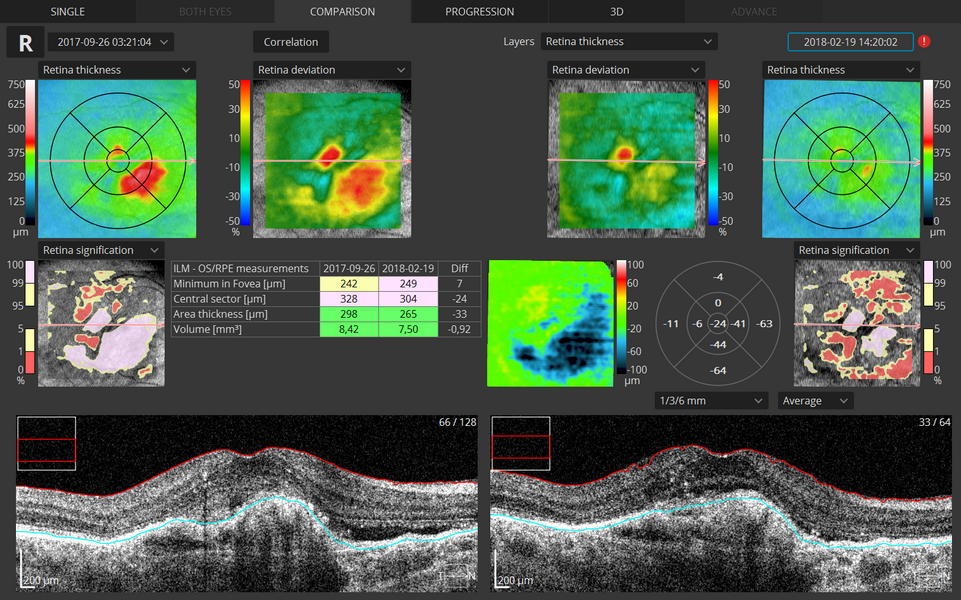

Η ΟCT είναι απολύτως απαραίτητη εξέταση προκειμένου να εκτιμηθεί η ανταπόκριση της θεραπείας με ενδοϋαλοειδικές εγχύσεις anti-VEGF παραγόντων και να ληφθεί απόφαση για επανάληψη της θεραπευτικής αγωγής σε ασθενείς που πάσχουν από υγρή μορφή Ηλικιακής Εκφύλισης της Ωχράς.

- Διαβητική Αμφιβληστροειδοπάθεια - Ωχροπάθεια

Η ικανότητα εκτίμησης του πάχους του αμφιβληστροειδούς και της αντικειμενικής καταγραφής του ενδοαμφιβληστροειδικού οιδήματος καθιστούν την εξέταση πολύ χρήσιμη στην παρακολούθηση του διαβητικού οιδήματος της ωχράς.